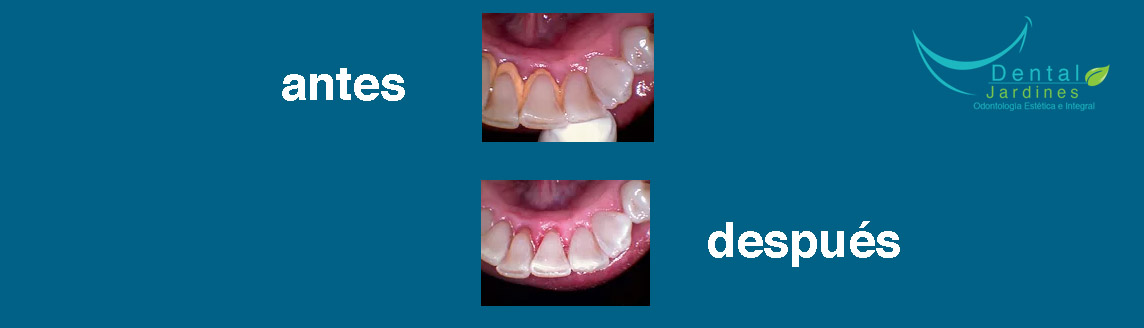

Nuestro objetivo principal es la calidad en nuestros tratamientos por lo cual te ofrecemos una consulta en la cual se te dará el tiempo suficiente para que el procedimiento tenga el mejor resultado. Nuestros tratamientos llevan un registro radiológico y fotográfico para que puedas observar el cambio en una foto de antes y después para lograr la satisfacción de nuestros pacientes.